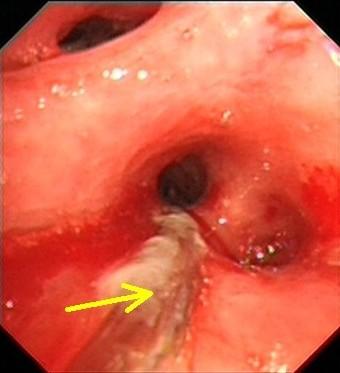

支气管扩张治愈不敢想?错!|咯血|气道|症状|治疗|杵状

支气管扩张图片

支气管扩张的症状图片

支气管扩张咯血图片